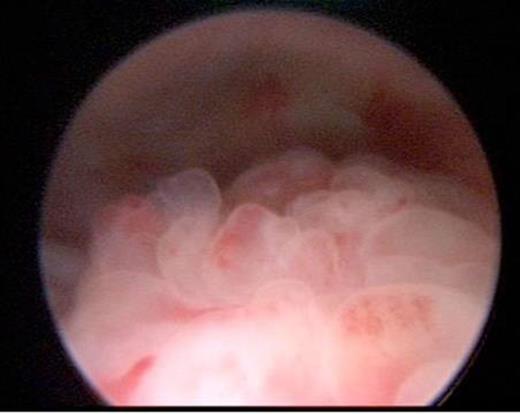

The diverticulum was clearly seen on micturating cystourethrogram (MCUG). Subsequent magnetic resonance imaging (MRI) scan confirmed the presence of a large bladder diverticulum and also demonstrated an enhancing, irregular, nodular posterior bladder wall thickening which was confined to the bladder. Cystoscopy revealed a papillary lesion on the posterior bladder wall adjacent to the diverticulum opening (figure 2).

The cystoscopic appearances resembled a rhabdomyosarcoma. Endoscopic biopsies demonstrated no evidence of malignant change. Diverticulectomy and ureteric re-implantation were performed to resolve bladder outlet obstruction and an open bladder biopsy of the lesion was conducted at the same time. Histological appearances were consistent with polypoidal cystitis. Immunohistochemistry was negative on conventional immunostains for rhabdomyosarcoma (i.e. desmin and cytokeratin). The patient made an uneventful recovery and continues to do well with no further episodes of urine retention at outpatient review.